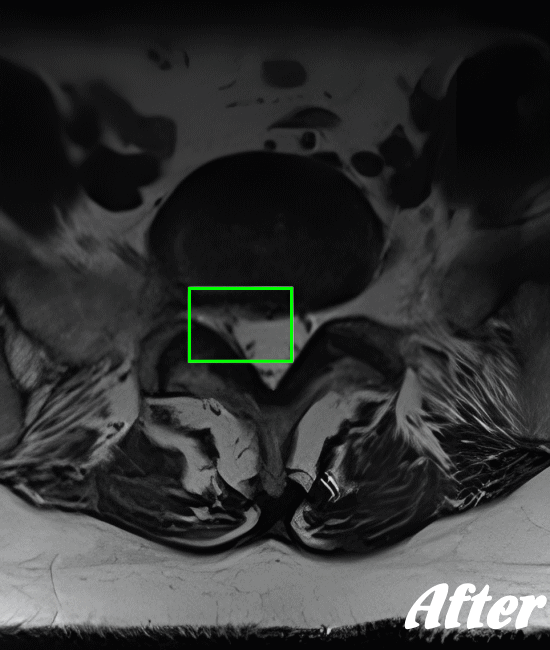

| 施術前(MRI) | 施術後(MRI) |

![]() |